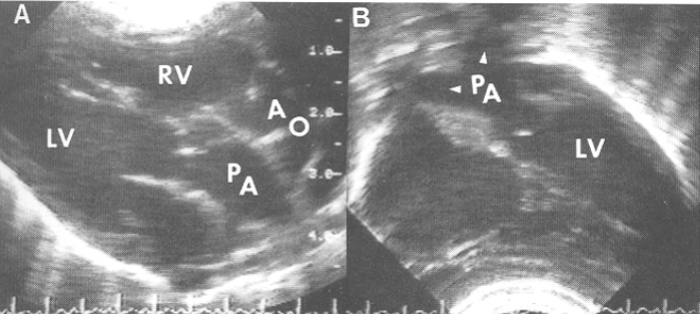

Transposition of Great Vessels (TGV)(TGA)(TOGV)

Dx when the Ao is anterior to the Pulm A

PSAX

2 types of TOGV:

D-Transposition

D-Transposition of the Great Vessels (DTGV)

there is one wrong connection / mismatch

correct atrium is connected to correct ventricle

the wrong great vessel is attached to each ventricle

aka complete transposition

unsaturated bl→RA→RV→ Ao

saturated bl→LA→LV→PA

associated w/ cyanosis

must have large ASD, VSD, or PDA to survive